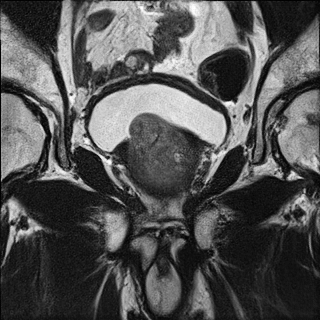

Refer to caption

(a) LR input to SRGAN 8x

(b) SRGAN 8x

Figure 5: SRGAN result for 8×8\times upscaling compared to LR input

Fig. 4 contains an example SR output for each method and the LR and HR images for reference. The LR image is severely pixelated and has no edge fidelity. While the image produced via bicubic interpolation has no pixelation, this method is still unable to preserve the high frequency information found in the ground truth image. The Sparse Representation method produces slightly better results than the previously discussed methods. However, the large amount of space and time overhead required by this model precludes it from clinical use. The SRCNN begins to show edge preservation, however the features within different regions of the output SR image are smoothed out. The SRCNN is especially biased toward smoothing the image because the network only uses MSE loss. The SRResNet has both MSE and perceptual loss yet fails to outperform the SRGAN. Clearly, the discriminator network seeks out the high frequency information that differentiates HR and LR images, thus forcing the SRGAN output to have far more high frequency details than the output of the SRResNet. The SRGAN 8x network is not able to maintain as high an edge fidelity as the SRGAN 4x network. This result is expected because the SRGAN 8x network is provided with far less information since the input LR image is a further 2x smaller in both dimensions (Fig. 5). Overall, in comparing the SRGAN to the other models, the outputs from the SRGAN are visually closer to the original HR ground truth images.